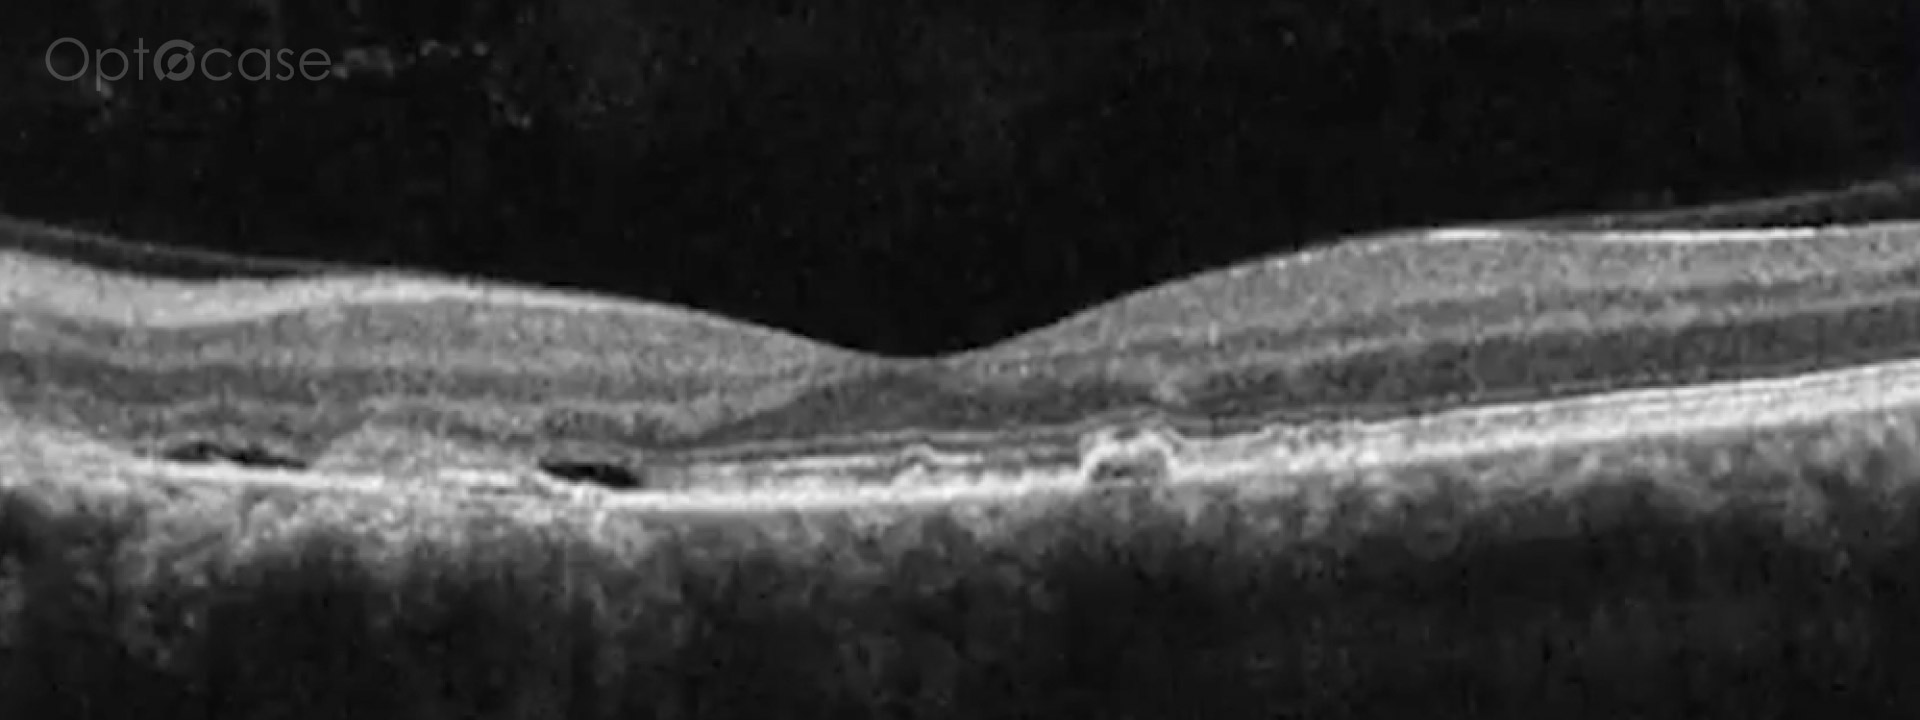

This patient presented with vertical diplopia, normal visual acuity, no afferent pupillary defect, and full extraocular movements. He was unable to fuse Maddox rod lines with prisms except for transient fusion at distance with prisms. His OCT was normal on the right eye, but showed evidence of a past central serous retinopathy (CSR) treated with photodynamic therapy.

The patient was diagnosed with dragged-fovea diplopia syndrome.